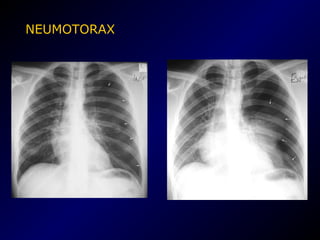

NEUMOTORAX

• El neumotórax espontaneo es frecuente en

varones normales

Causas

• Bulla o bleb

• EPOC

• Lesiones intersticiales pulmonares

• Neoplasias

• Trombo embolismo pulmonar

• Traumatismo

NEUMOTORAX A TENSION

• Efecto de válvula

• Clínica.- dolor

pleural de instalación

súbita, seguido de

disnea cuya

intensidad depende

de la magnitud del

neumotórax.

• EXPLORACION FISICA:

– Inspección.- hemitórax abombado

– Palpación.- vibraciones vocales disminuidas

– Percusión.- hipertimpánico

– Auscultación.- murmullo vesicular disminuido o

abolido.

• SIGNOS RADIOLOGICOS

– Línea fina producida por la pleura visceral separada de

la pleura parietal por un espacio lleno de aire

– Ausencia de trama vascular

– Imagen hipertransparente

– Desplazamiento cardiaco contralateral

– Desvío traqueal contralateral